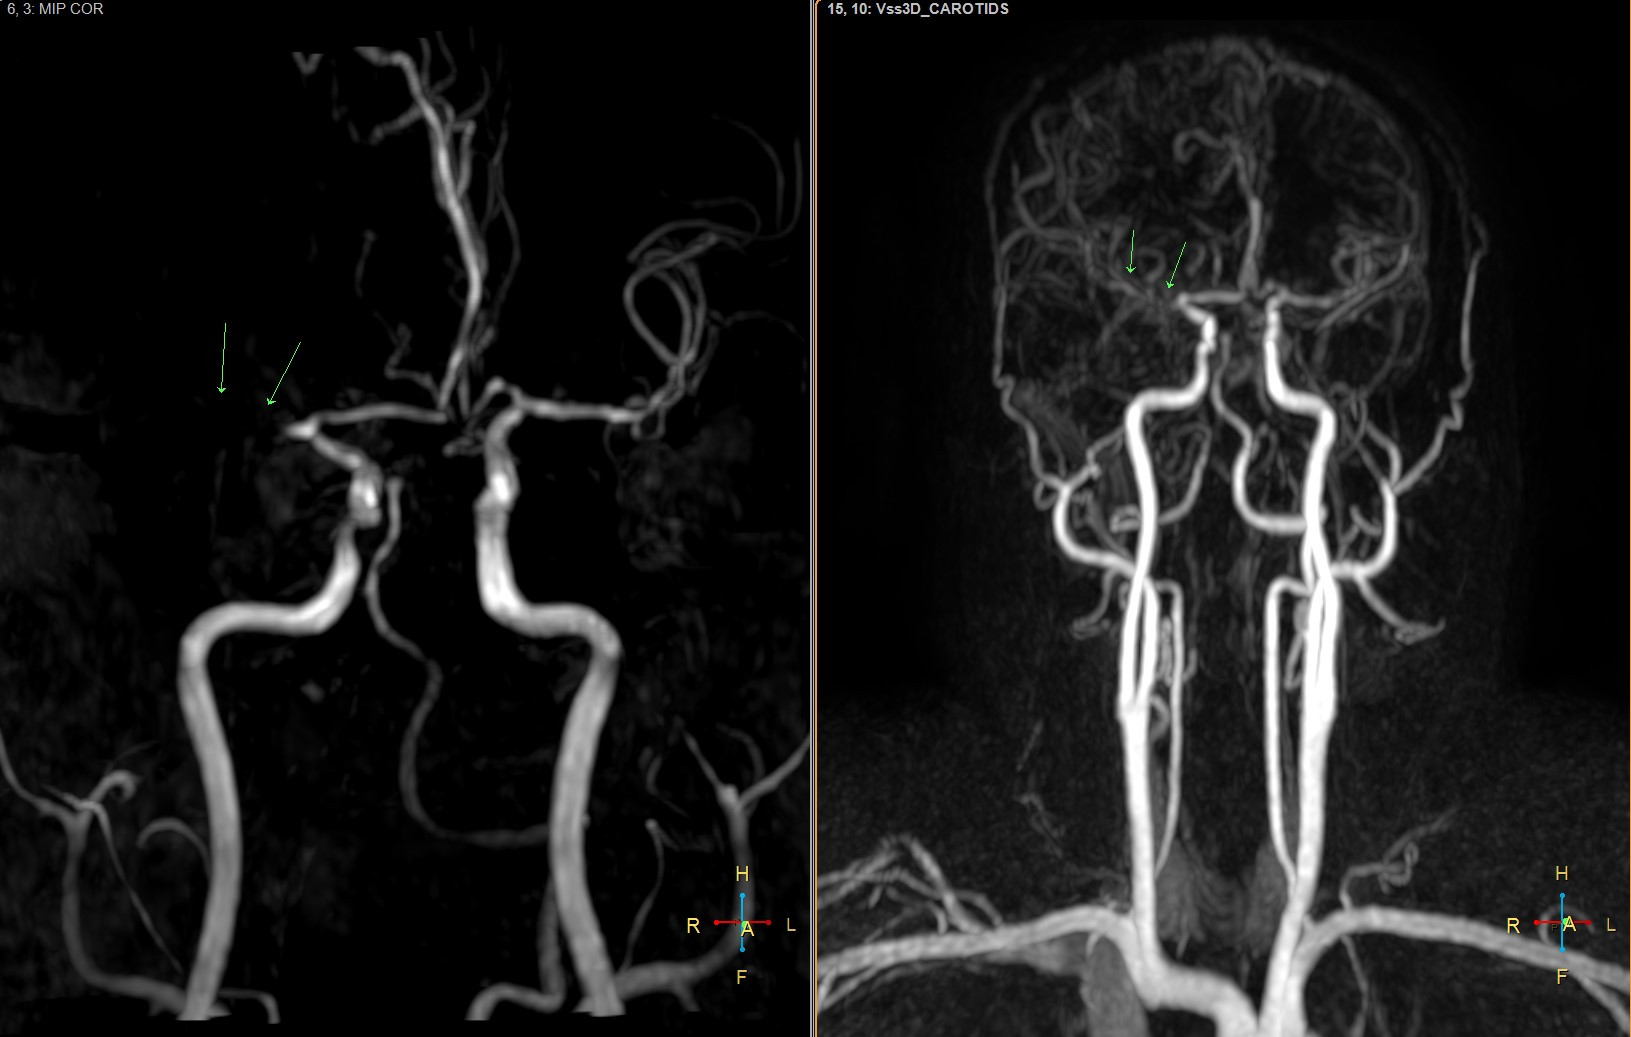

Trong lĩnh vực thần kinh, CHT hỗ trợ chẩn đoán đột quỵ cùng các bệnh lý u não, u dây thần kinh sọ não, chấn thương sọ não hay viêm não. Trong quá trình thăm khám, các bác sĩ tại Bệnh viện đa khoa Vạn Hạnh phát hiện nhiều trường hợp hẹp động mạch não, có nguy cơ cao dẫn đến đột quỵ não, từ đó tư vấn người bệnh cách điều trị phù hợp nhằm giảm thiểu rủi ro.